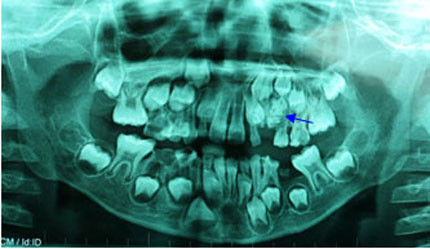

| 76 chiếc răng trong miệng bé 7 tuổi |